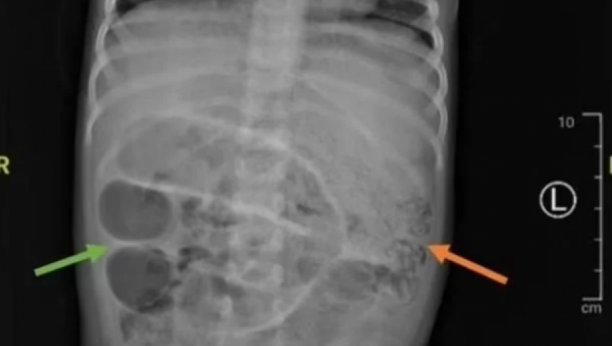

Dijagnoza je, prema rečima medicinskog osoblja, u početku bila blokada creva.

Tokom operacije, lekari su identifikovali i uklonili brojne crve Ascaris lumbricoides , dugačke nekoliko centimetara, koji su stvorili "gužvu" u tankom crevu deteta.

- Rez napravljen za uklanjanje parazita napravljen je na tački otprilike 50 centimetara od debelog creva. Crvi su poslati na dalju analizu u laboratoriju. Istovremeno, analize krvi su pokazale da dete boluje i od anemije, česte pojave u ovakvim slučajevima. Paraziti apsorbuju značajan deo gvožđa i drugih hranljivih materija u telu, uzrokujući, između ostalog, probleme u razvoju deteta. Mladom pacijentu je određena terapija antibioticima, hidratantnim rastvorima i preparatima protiv crevnih parazita. Otpušten je nedelju dana kasnije - prenose mediji.